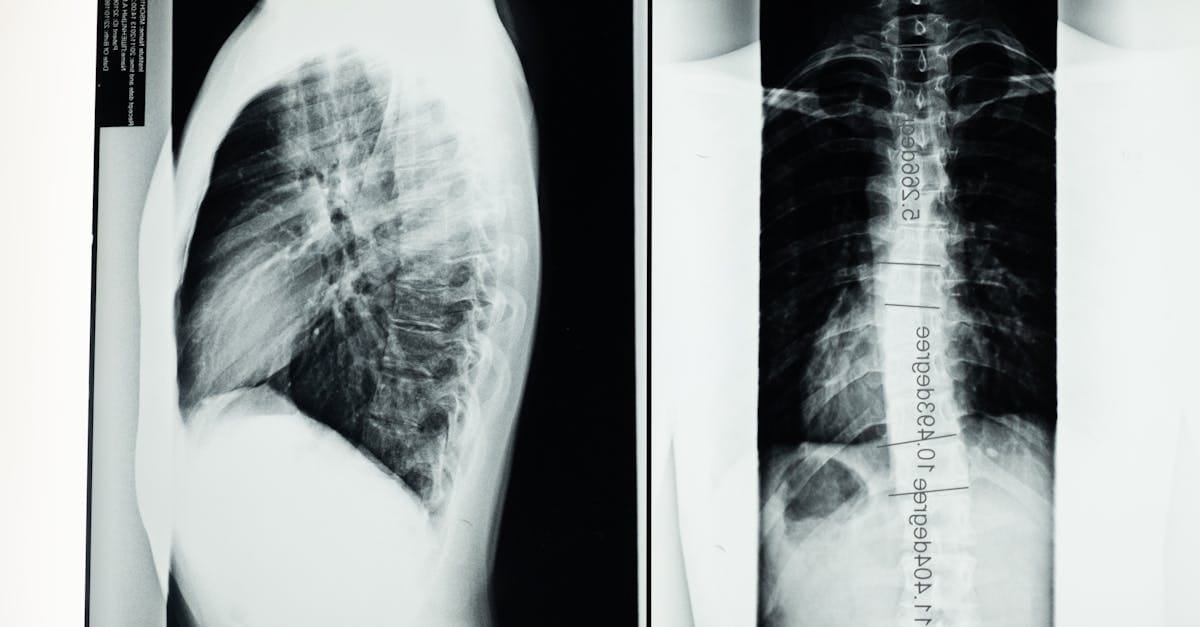

Evaluation of Candidates for Spinal Decompression

Before starting a decompression treatment, it is essential to perform a comprehensive evaluation of the patient’s health condition. This evaluation typically includes clinical examinations and imaging techniques to characterize the severity of the disc herniation. Healthcare professionals must also consider the patient’s medical history, taking into account other pathologies or previous treatments.

Un examen clinique approfondi et des imageries comme une IRM ou une radiographie sont souvent nécessaires.